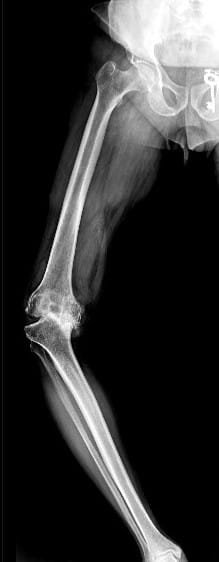

Osteoarthritis (OA) of knee occurs due to wear and tear of cartilage. It is usually due to aging and seen mostly in elderly people. Females usually get affected at slightly earlier age than males. OA can also occur in some cases due to injury in the knee, congenital malformation or due to any other diseases affecting other joints of the body.

It is due to progressive wear and tear leading to loss of cartilage in knee joint. Most commonly, this is due to the aging. In some cases, damage to the cartilage may occur due to rheumatoid and other inflammatory arthritis, trauma, infection, gout, or any other condition affecting knee joint. Those who are over-weight have more chances of developing arthritis in their knees.

Your doctor will do clinical examination of knee joint, hip joint, spine and other joints of your body. X-rays of both knees will be performed. Occasionally, MRI of the Knee joint and few blood investigations may be required as per their underlying problem.